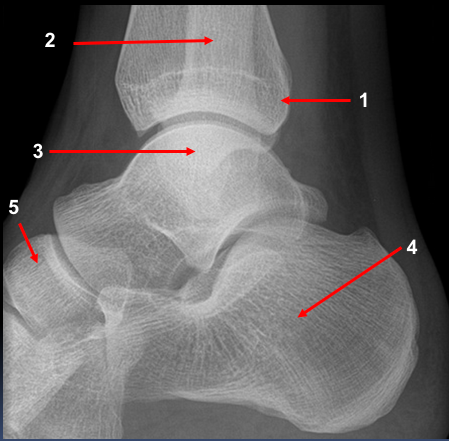

A 25 year old man presented to the ED with right ankle pain after a fall.

He was struggling to walk. His ankle was swollen and tender on examination. Movement was limited due to pain.

What can you see? What injuries are present?

A 30 year old woman presented to the ED with right ankle pain after a fall. She was struggling to walk. Her ankle was swollen and tender on examination. Movement was limited due to pain.